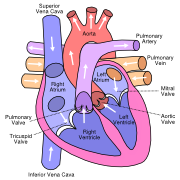

| 18:23, 9 October 2012 | Diagram of the human heart (valves improved).svg (file) |  |

27 KB | Source:http://commons.wikimedia.org/wiki/Image:Diagram_of_the_human_heart_%28cropped%29.svg | 2 |